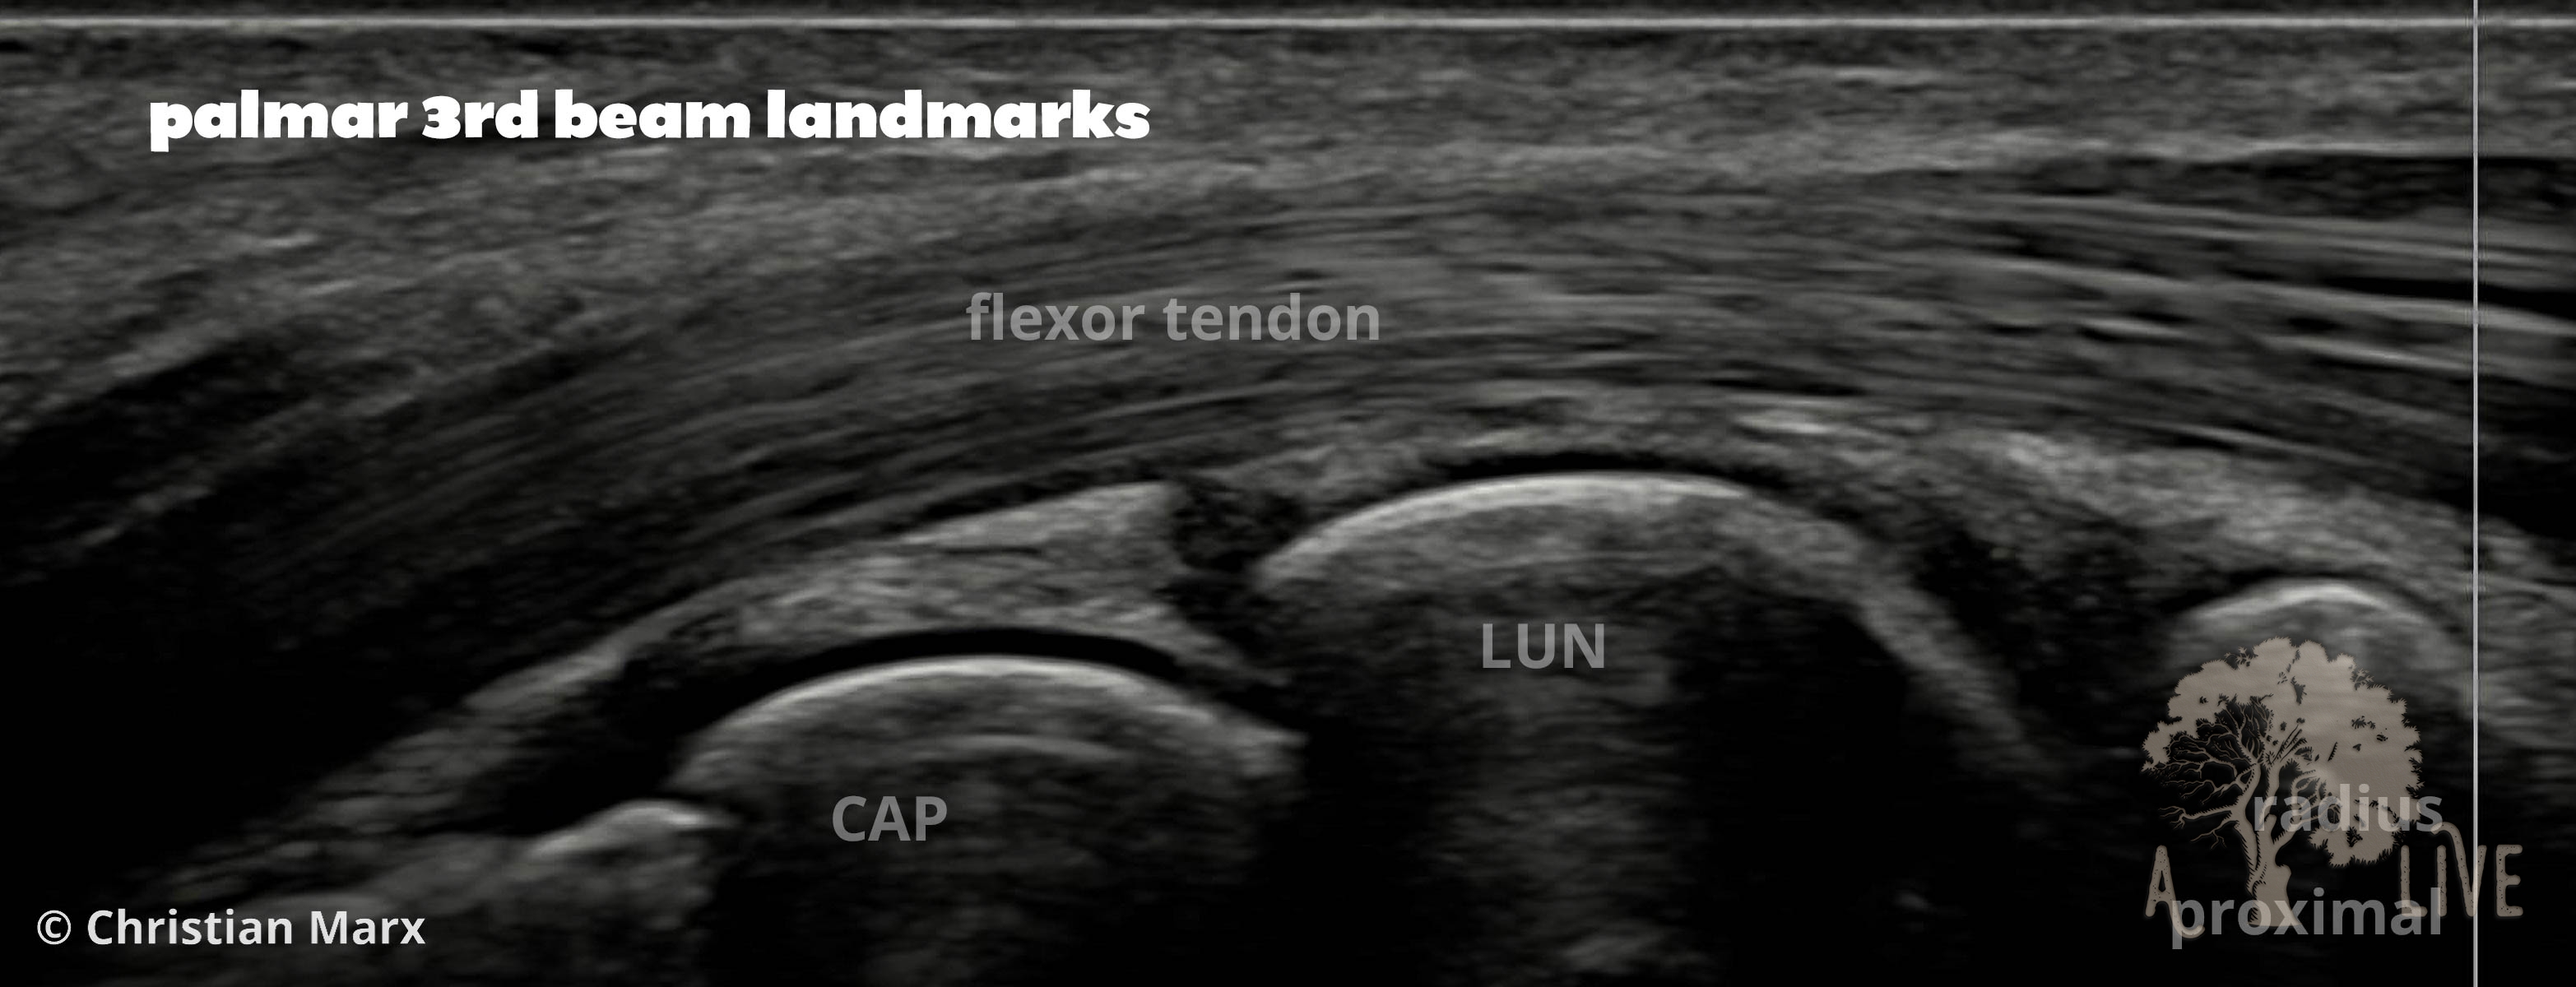

carpal ligaments